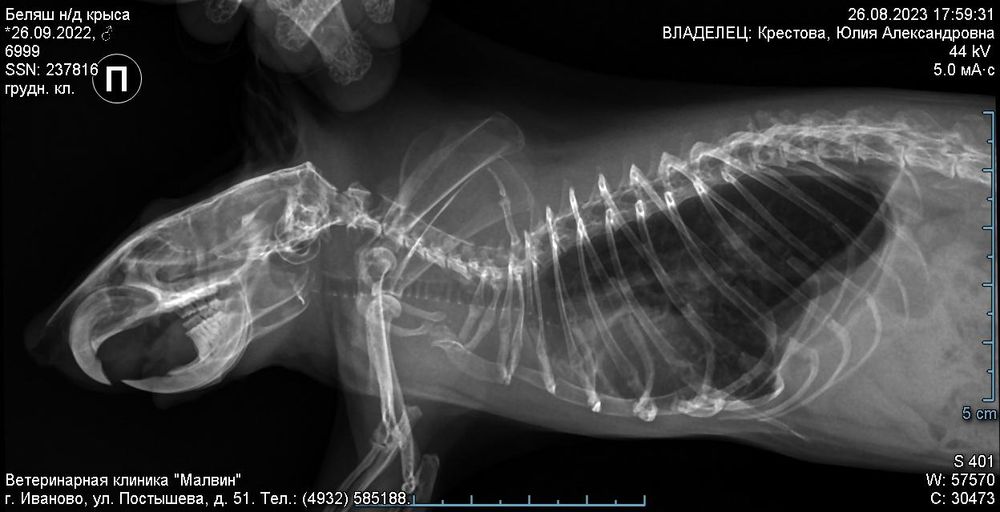

Рентген.